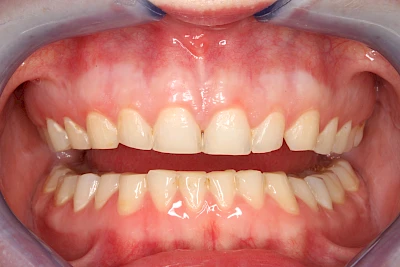

Über die Zeit können verschiedene Prozesse die Zahnhartsubstanzen aufzehren:

- Abnutzung durch Kauen (Abrasion) oder duch durch übermäßiges Knirschen bzw. Pressen (Attrition)

- Säurebedingte Auswaschung (Erosion)

- Knirschen bzw. Pressen und ungünstige Putztechnik (Druck): keilförmige Defekte